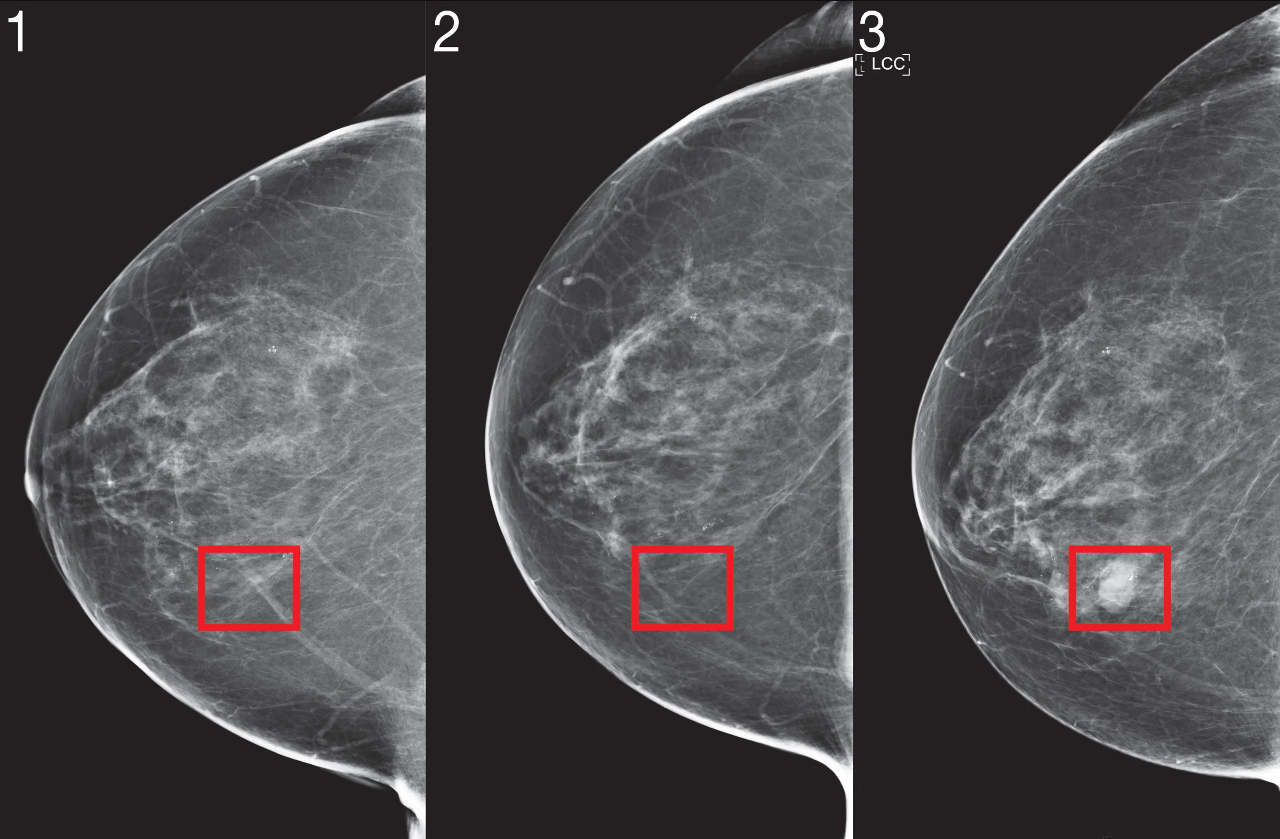

– Chụp nhũ ảnh: Chụp nhũ ảnh có thể phát hiện các khối u ở vú trước khi chúng có thể được cảm nhận.